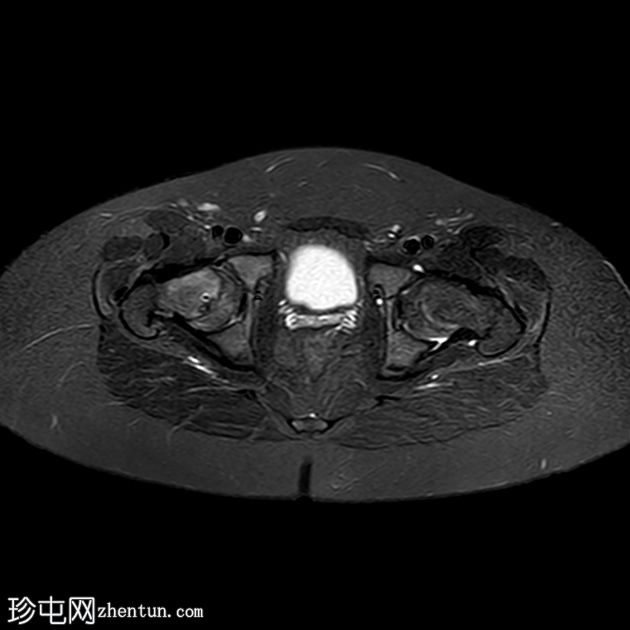

MRI

轴位片

T1加权像

双侧股骨近端骨骺皮质不规则,轻度增宽,伴股骨骨骺及近端干骺端骨髓水肿。

双侧股骨骨骺轻度后内侧移位。

双侧轻度髋关节积液。